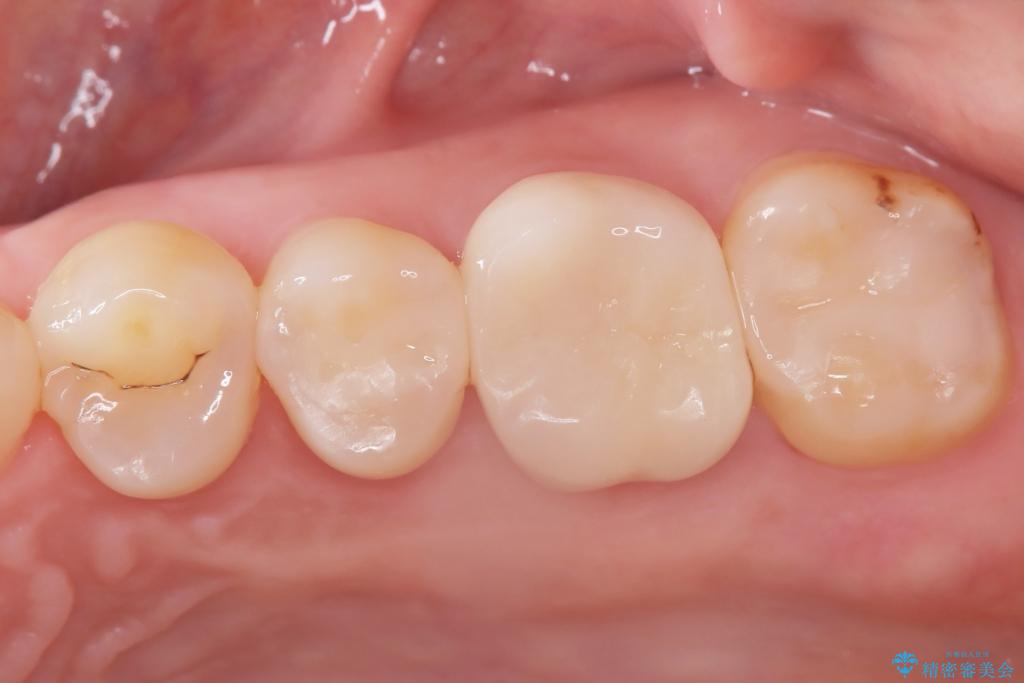

今回の治療では、虫歯の大きさや深さに応じて、異なるセラミック修復法を適用しました。

比較的軽度な虫歯には、セラミックインレー(詰め物)で対応し、健全な歯質を最大限に残しました。

進行した虫歯や歯の強度が低下している歯には、セラミッククラウン(被せ物)を選択し、歯全体を保護することで破折を防ぎました。

短期間での治療を可能にしつつ、天然歯と見分けがつかない審美性と、長期的に安定する機能性を兼ね備えたセラミック修復を実現しました。